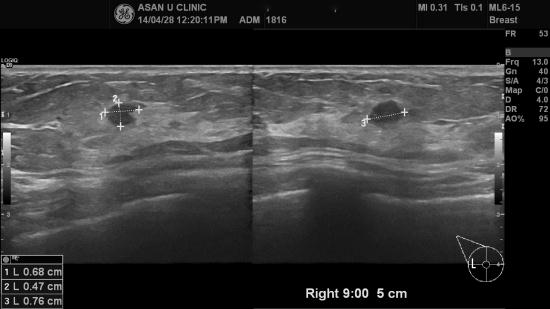

아산유외과 개원 후 94번째 유방암진단.

검진센타에서 의뢰된 59세 여성분입니다.

우측 유방에, 0.7cm의 혹이 있었고 인근에

0.5cm 의 혹도 의심스러워 조직검사를 함께 시행하여

각각 유관의 상피내암, 비정형 유관증식으로 진단되었습니다.

초기에 진단이 되어 다행이라 여겨지는 증례였습니다.